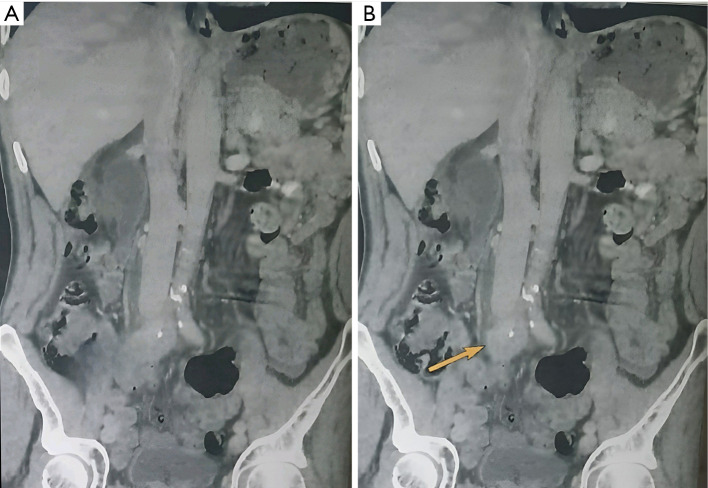

Case description: We present the case of a 64-year-old male patient from Casablanca with no notable medical history who reported right low back pain without accompanying fever and exhibited signs of a deteriorating general condition. Clinical examination revealed tenderness upon palpation of the right flank and a left thyroid nodule. Ultimately, a diagnosis of RPF secondary to prolonged occupational asbestos exposure was established. The patient underwent the insertion of a right JJ stent and received combined corticosteroid therapy.

Abstract Image